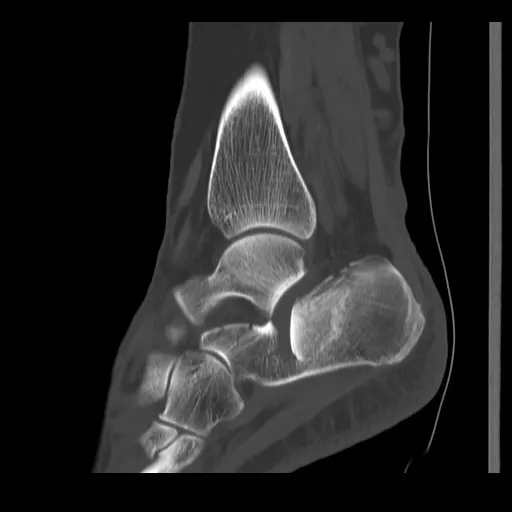

Een röntgenfoto van de voet en hiel toont meestal duidelijk de calcaneusfractuur en in welke mate de botstukken verplaatst zijn. De arts bekijkt ook of het enkelgewricht en het onderste spronggewricht (onder de enkel) bij de breuk betrokken zijn. Bij complexe of verplaatste calcaneusfracturen wordt vrijwel altijd een CT-scan gemaakt om een driedimensionaal beeld van de breuk te krijgen. Dit helpt bij het plannen van de behandeling.